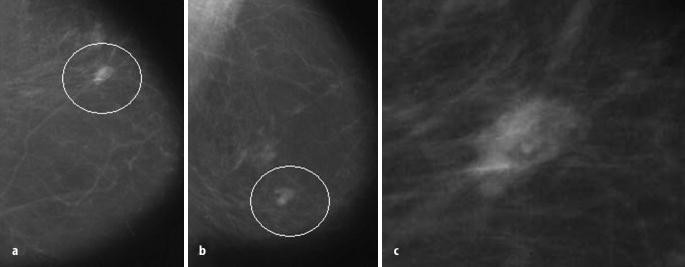

Brustkrebs Mikroverkalkungen der Brust können auf einen Tumor im Frühstadium hinweisen Bei Früherkennung sind die Heilungschancen sehr hoch. Brustkrebs Mikroverkalkungen der Brust können auf einen Tumor im Frühstadium hinweisen Bei Früherkennung sind die Heilungschancen sehr hoch. 3 stromal Verkalkungen in der Brust sind in der Haut, Fettzysten lokalisiert, die in der Wand der Blutadern, Fibroadenome Sie sind groß, glybchatye, unförmig, die Art der „Popcorn“, leicht zu diagnostizieren Klein wie Verkalkung von Fibroadenome, wie „Schutt“, erfordert eine weitere Diagnose –.

Brustkrebs Mikroverkalkungen der Brust können auf einen Tumor im Frühstadium hinweisen Bei Früherkennung sind die Heilungschancen sehr hoch. Bei einer Mammografie können Kalkablagerungen in der Brust entdeckt werdenDiese Mikroverkalkungen treten häufig während der Wechseljahre auf In den meisten Fällen sind die Verkalkungen nicht gefährlich Ein Restrisiko besteht natürlich, Kalk in der Brust kann in seltenen Fällen ein Frühzeichen für eine Krebserkrankung seinIn diesem Fall wird der Radiologe der. Das Ziel einer Mammographie besteht darin, eine bösartige Erkrankung auszuschließen bzw sie so früh wie möglich zu erkennen Sie ist dann sinnvoll, wenn Sie oder Ihr behandelnder Arzt eine verdächtige Veränderung an der Brust bemerken, zum Beispiel tastbare Verhärtungen (Knoten) in der Brust oder geschwollene Lymphknoten in der Achselhöhle 2.